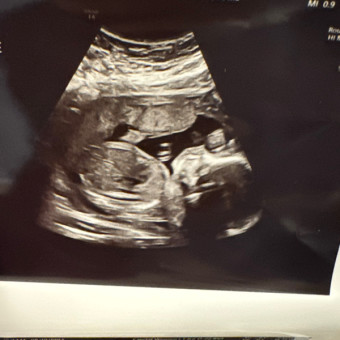

Yvette's & Josh’s Baby Registry

Yvette Olivarez & Josh Stramberg

Derwood, MD

August 6, 2024

Thank you for sharing with us as we embark on our second journey through parenthood. Giddy is super excited to share the love with his baby brother.